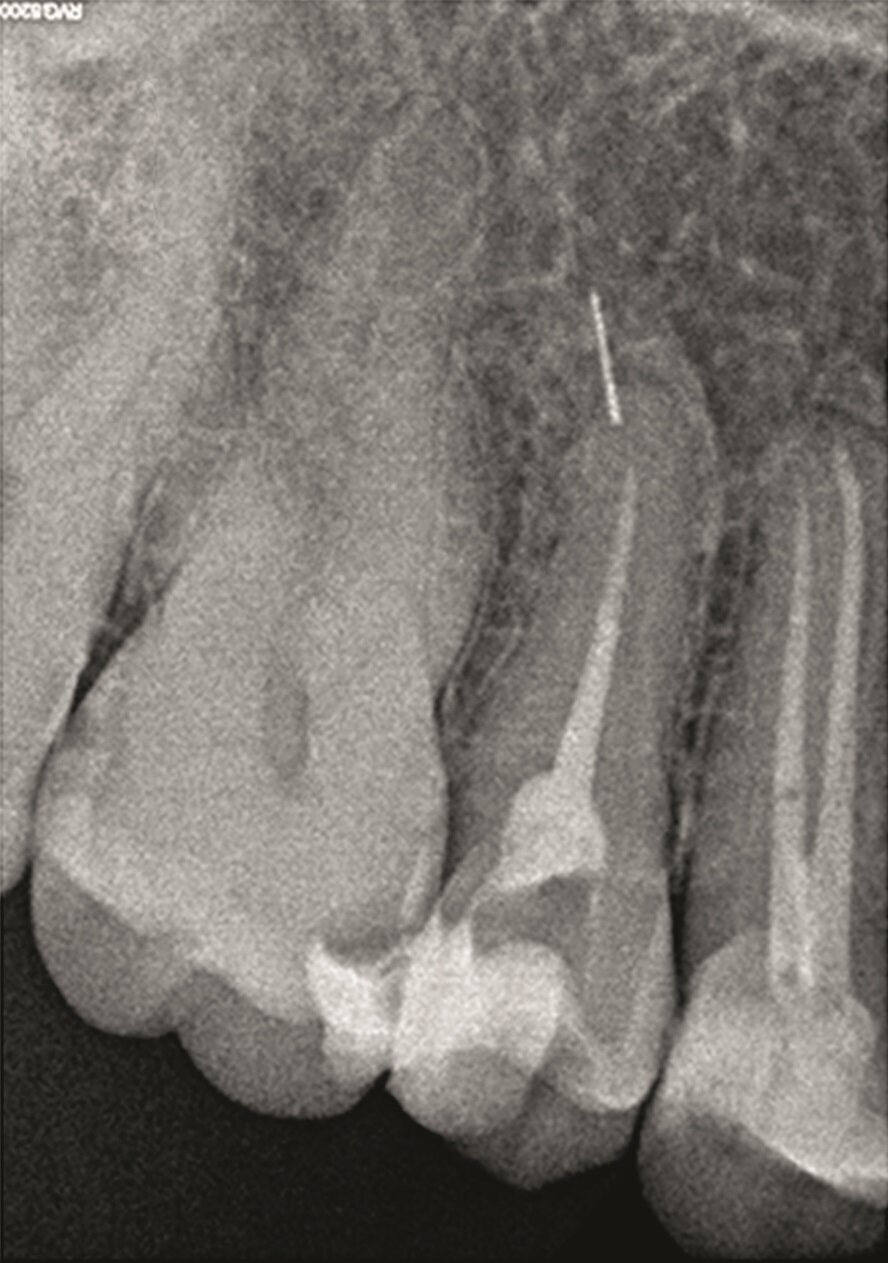

A 38-year-old female patient consulted owing to moderate pain associated with her previously treated maxillary right second premolar. Her medical history was non-contributory. Clinical examination revealed that the tooth was slightly sensitive to vertical percussion. Periodontal probing depth and mobility were within normal limits. A periapical radiograph showed the presence of a separated instrument outside of the root (Fig. 2a), and a preoperative CBCT scan demonstrated that the buccal bone plate was intact (Figs. 2b & c). Endodontic retreatment had been performed five months earlier. The diagnosis for tooth #15 was previously treated symptomatic periapical periodontitis, and the treatment of choice was guided EMS.

Fig. 2k: Post-op radiograph after apicectomy, retro-preparation and retro-filling with TotalFill BC RRM Fast Set Putty.

Fig. 2m: Two years follow-up radiograph.